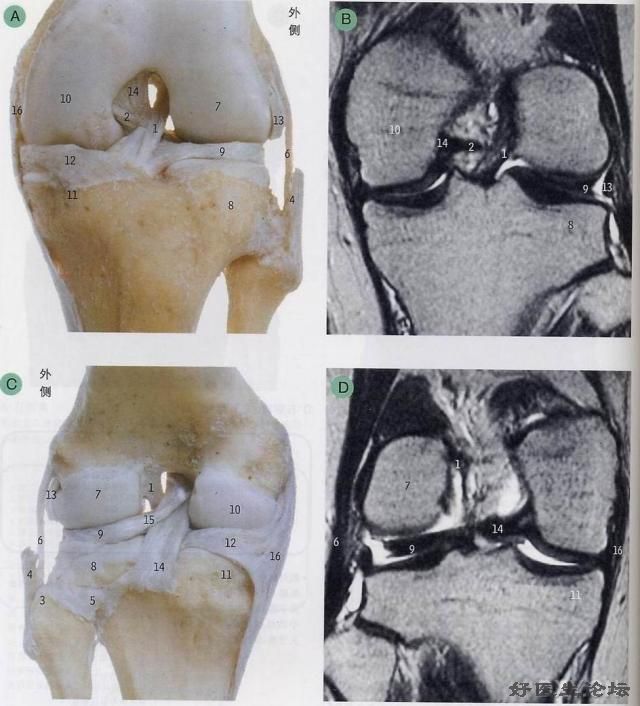

影像学检查

* CT

* MRI

MRI   MRI   MRI